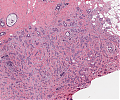

A82 Appendix-Karzinoid

Große, nestartige Verbände neuroendokriner Tumorzellen

A82 Appendix-Karzinoid

Tumorzellnester und diffuse Infiltration der neuroendokrinen Tumorzellen

Appendixkarzinoid

Erkennbar sind isomorphe Tumorzellnester

Appendixkarzinoid

Neuroendokriner Tumor mit nestartigen, trabekulären Formationen isomorpher Tumorzellen